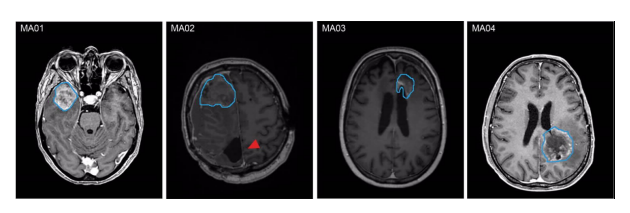

MA01-03為WHO Ⅳ級IDH野生型膠質(zhì)母細胞瘤;MA04為WHO Ⅳ級星形細胞瘤IDH突變體。

圖1 不同患者MRI